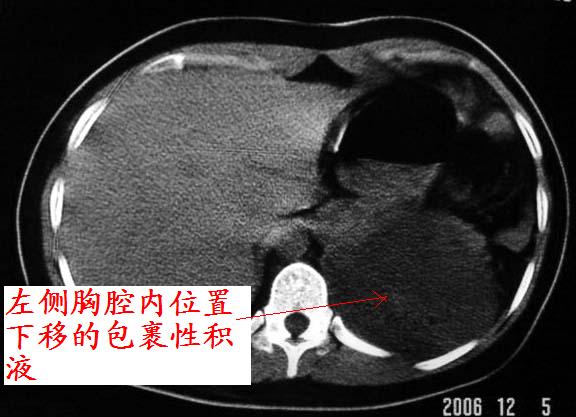

标题: CT5517:女性、24岁,反复胸痛、气促不能平卧半月。

左肺可见二个含气或液气的囊状影,左肺段支气管、左肺动脉显示不清,纵隔右移,考虑:左肺支气管肺囊肿,左肺发育不良,纵隔疝。

左侧气液腔与胃腔影相连,考虑膈疝。钡餐检查有助于诊断。

我看这是膈疝,在纵隔窗第六\\七幅图像上可见胃粘膜影,再者可见两个腔影,这在液气胸是不会有的.

综合分析考虑:1左侧包裹性液气胸。2左侧胸膜肥厚。3左肺膨胀不全